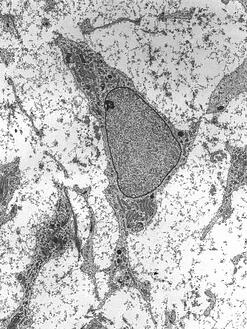

(Image of adult stem cell by Robert M. Hunt)